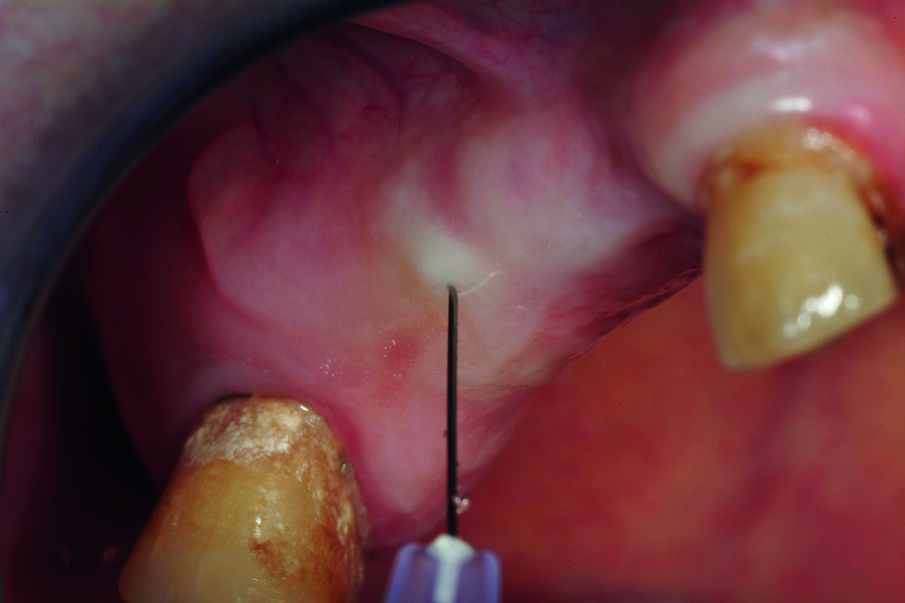

Terapia chirurgica

La tecnica chirurgica scelta permetterà di ridurre la durata dell’intervento e il rischio operatorio: sanguinamento, calo di glicemia, rischio di infezioni. È stato utilizzato un anestetico con una bassa concentrazione di adrenalina al fine di evitare un effetto iperglicemizzante ed è stata eseguita una terapia preventiva della sepsi per evitare qualsiasi rischio al paziente diabetico (Figg. 3a, 3b).